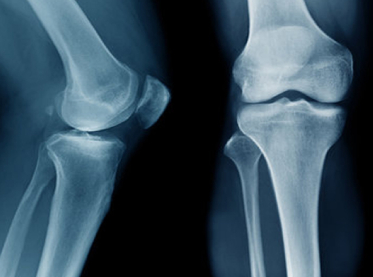

X-rays provide detailed images of internal structures, allowing healthcare providers to accurately diagnose a wide range of medical conditions, including fractures, pneumonia, tumors, and dental issues.X-ray images provide valuable guidance for treatment planning and monitoring. They help healthcare providers determine the most appropriate course of action for conditions such as fractures, dislocations, and dental problems.